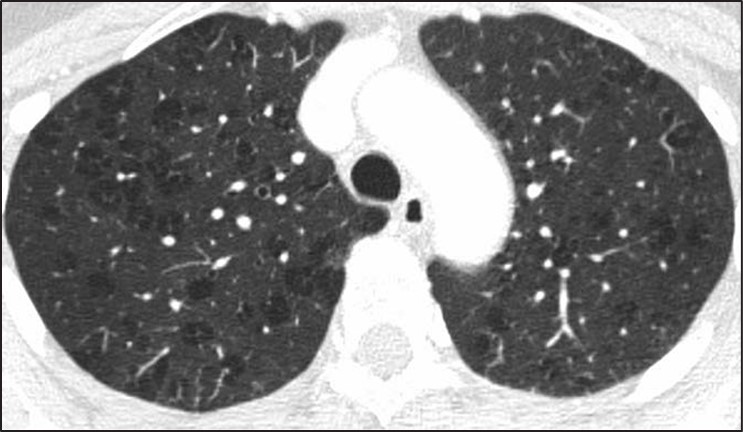

Many of the pitfalls in correctly identifying honeycombing and distinguishing honeycombing from mimics can also be applied to the correct diagnosis of cystic lung disease. When considering a potential diagnosis of cystic lung disease, it is important to again identify mimics: honeycombing, dilated airways and bronchiectasis, and emphysema. The extent of abnormality, from mild to severe, is also important to consider in this context. A few scattered pulmonary cysts may be considered in the spectrum of normal, particularly for older patients, and are most likely postinfectious rather than indicative of a cystic lung disease [14].Whereas the primary features of bronchiectasis (i.e., tubular shape) and honey- combing (i.e., thick walls, clustered, subpleural) make distinguishing these entities from cystic lung disease more straightforward, correctly distinguishing cystic lung disease from emphysema can be challenging. This challenge is in part because both entities can have very thin or imperceptible walls and can occur on a spectrum from mild to severe. The presence of the “central dot” sign in which the centrilobular artery is seen within an emphysematous space can be helpful in correctly distinguishing centrilobular emphysema from a cystic lung disease; however, this finding is not reliably seen in all regions of emphysema [15] (Fig. 6).

Fig. 6—Axial HRCT scan shows “central dot” sign in patient with centrilobular emphysema.

In general, pulmonary cysts are fewer in number, noncentrilobular in distribution, and have thicker or more perceptible walls compared with centrilobular emphysema [16]. Paraseptal emphysema and panlobular emphysema are less frequently mistaken for cystic lung disease because of their strongly subpleural distribution and overall extent respectively.